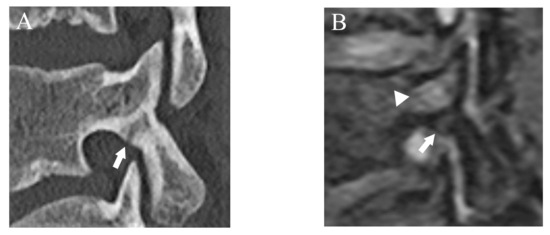

Figure 2.

Representative images of grade 2 fracture. The left pars interarticularis of L5 from a 16-year-old male. (A) Sagittal CT image showing an incomplete but clear fracture line starting from the caudal part of the pars interarticularis (arrow). (B) Sagittal DESS image showing a linear high signal that suggests the fracture line (arrow).

Figure 3.

Representative images of grade 3 fracture. The right pars interarticularis of L5 from a 16-year-old male. (A) Sagittal CT image showing a complete fracture across the whole pars interarticularis (arrow). (B) Sagittal DESS image showing a linear high signal corresponding to the complete fracture (arrow).

After more than a 2-week interval from creating standard references, two readers independently analyzed fractures on T1WI and DESS using the same grading system as used in CT. On MRI, bone resorption (grade 1) can be detected as slight hyperintensity within cortical bone which normally shows homogeneous hypointensity (Figure 1). The fracture line on MRI is delineated as linear hypointensity on T1WI and linear hyperintensity on DESS (Figure 2 and Figure 3). DESS was also used to evaluate the BME binary. Similar to STIR, if there is a high signal at pars interarticularis on DESS, it is considered positive for BME. Consensus results for T1WI, DESS for fracture and DESS for BME were created for statistical analysis.